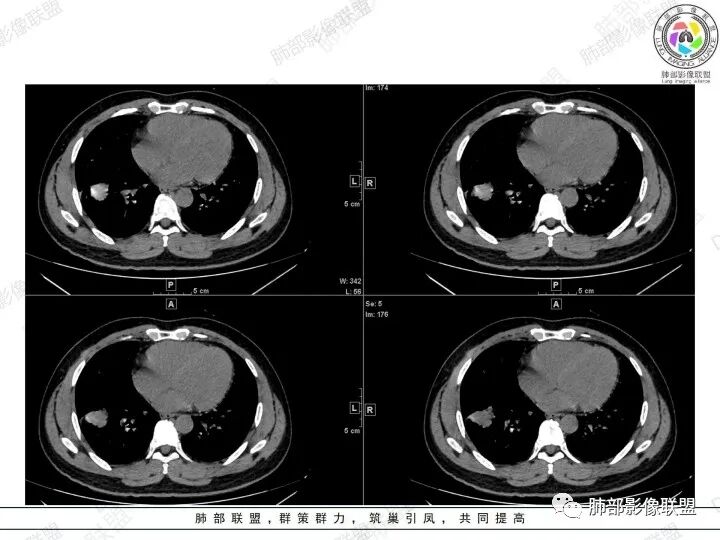

2、胸部CT右肺下叶胸膜下肿块性病变,边缘可见分叶毛刺、边缘膨隆,似有指状凸起,邻近胸膜稍牵拉凹陷,叶间裂以为不明显,提示收缩力较弱。近端支气管进入后截断,病灶内密度尚均匀,增强后可见轻度强化,未见空洞或钙化,并可见血管影进入。右侧肺门及纵隔内可见肿大淋巴结影。无胸腔积液。

3、综合患者临床症状及影像表现,需要考虑肿瘤性病变和非肿瘤性病变,肿瘤性病变需要考虑普通浸润性腺癌或结节型粘液腺癌、淋巴瘤、淋巴上皮瘤样癌、小细胞肺癌等,非肿瘤性病变主要考虑肺脑同病中的隐球菌。①普通浸润性腺癌,以肺外周多年、混合磨玻璃或实性结节/肿块,多见分叶、毛刺、胸膜凹陷、血管集束等征象,本例收缩力较弱、且强化偏轻,不够典型。②粘液腺癌,腺癌的特殊类型。多位于胸膜下(90%位于胸膜下,70%位于下叶胸膜下),边缘清或不清的GGO:提示粘液外渗,少数为纯GGO,缺乏中心纤维化区:毛刺、胸膜凹陷征少,很少胸膜侵犯,淋巴结转移少见,增强后无强化或低强化,本例病灶位于胸膜下,强化轻,收缩力弱,结节期粘液腺癌确实可以符合。③小细胞肺癌,吸烟男性多见,典型征象包括娘小崽大、腊肠样凸起、冰冻纵膈等,本例胸膜下病变大、但肺门淋巴结肿大程度较轻,不符合常见小细胞癌生物学行为,但有可疑指状凸起,小细胞肺癌不能完全除外。④淋巴上皮瘤样癌,少见的恶性肿瘤,患病年龄较轻,肿瘤多位于胸膜下,边缘多光滑,病灶周围可见磨玻璃,毛刺及分叶、胸膜凹陷少见,近端支气管可截断,增强多为中度-明显强化,本例除了强化程度偏轻外,影像表现基本可符合。⑤淋巴瘤,原发肺内淋巴瘤较少见,病灶多位于支气管血管束周围或胸膜下,密度多较均匀,边缘可膨隆也可平直收缩,可见支气管充气征、血管造影征等,强化多为轻中度,本例肺内结节血管穿行自然,局部有血管漂浮,长轴与支气管走行基本一致,肺门淋巴结肿大,不能排除。⑥隐球菌,影像表现可分为孤立结节型、大片实变型、多发结节或实变型、弥漫型。病变多位于胸膜下,边缘平直为主、可伴晕征,可见支气管穿行、部分可见支气管截断,密度多较均匀,部分可伴空洞,增强多为轻中度强化、延迟强化。本例病变位于胸膜下,收缩力弱,强化程度轻,但没有呼吸道症状,病变近端支气管截断,肺门淋巴结大,这些征象都难以用隐球菌解释,基本排除。